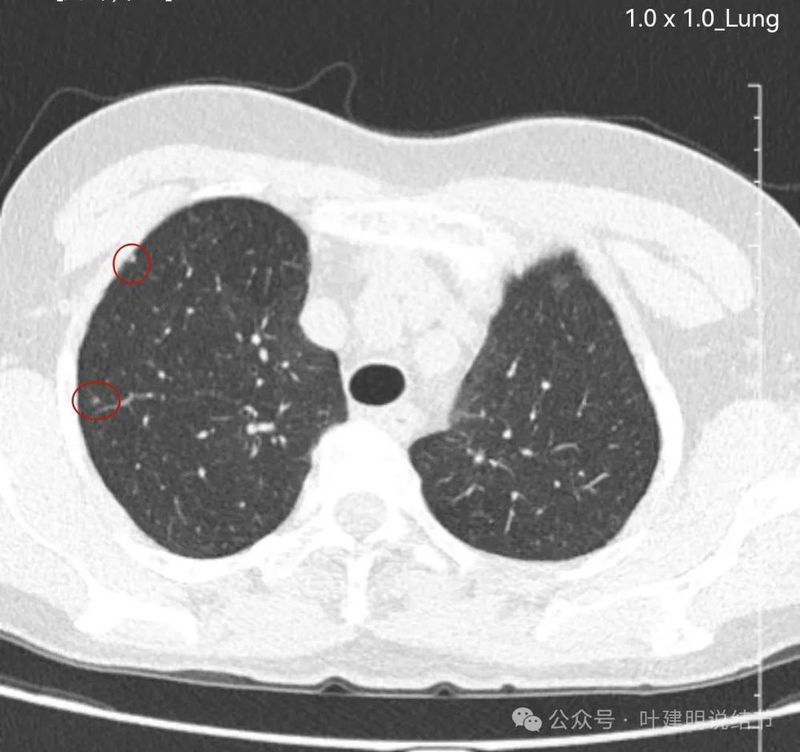

先来看两肺多发病灶的情况:

左上叶磨玻璃结节,密度稍不均,有部分偏实性成分,表面不平,轮廓与边界清,似有微小血管进入,恶性范畴的可能性大些。

右上叶磨玻璃结节,轮廓清,表面不平,不典型增生或原位癌可能性大。

右下叶胸膜下微小磨玻璃结节,有微血管征,轮廓与边界清,不典型增生可能性较大。